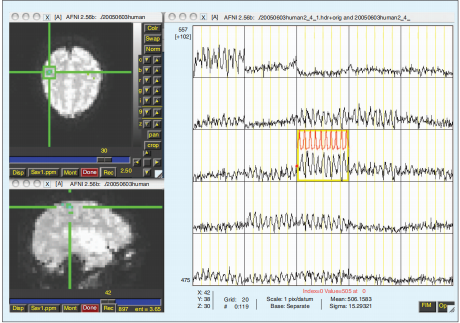

与功能连接分析不同,脑区域的功能定位关注于确定大脑中特定区域与特定功能之间的关联关系。这项技术旨在揭示大脑中在执行不同认知任务时活跃的区域,从而帮助我们理解大脑在特定功能上的工作机制。研究人员会让被试执行不同的认知任务,然后观察大脑在执行任务时的活动模式。通过分析fMRI数据,研究人员可以确定与特定任务相关的脑区域。脑区域的功能定位的目的是为我们提供了解大脑不同区域的功能分布和作用的重要手段,为我们理解大脑的工作原理提供了关键线索。[10][11]

图3.fMRI数据样本(来自交替搓手模式)。在240秒的时间内,受试者参与了一个交替休息6秒、左手挤压6秒、休息6秒和右手挤压6秒的模式。[12]